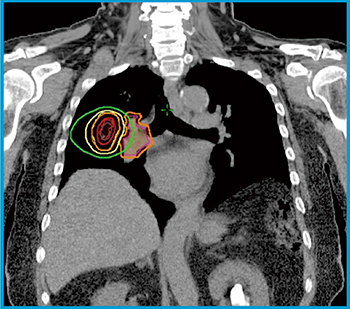

図5 右下葉転移性肺腫瘍

肺動脈と病巣が近接している。Timmermanらの定義によればcentral tumorである。しかし,PTVと肺動脈に3mm付与したPRVの最短距離が6mmであり,60Gy/5回(60% isodose)の線量処方でも,PRVへの線量はほぼ40Gy以下(D2cc40Gy),肺動脈への最大線量は40Gy未満である。そのため,60Gy/5回(60% isodose処方)にてSBRTを行った。

肺動脈(○),肺動脈PRV(+3mm)(○),GTV(○),PTV(○),等線量曲線は外側より20Gy(○),40Gy(○),60Gy(=処方線量)(○),80Gy(○)